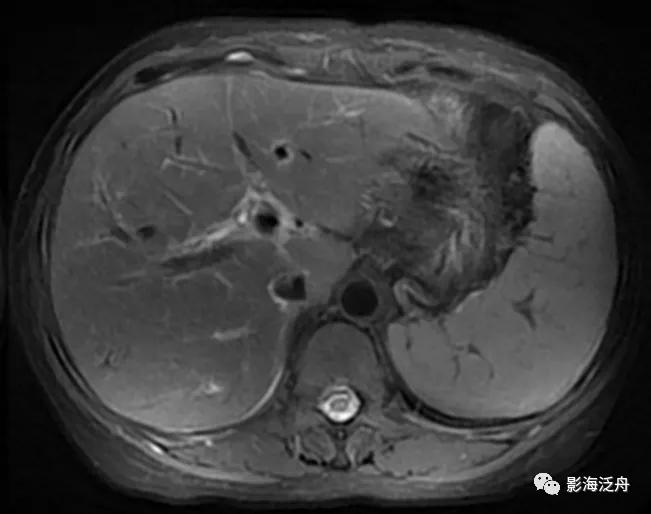

4.肝硬化

一例比较典型的肝硬化病例:T1WI上呈均匀稍高信号的再生结节(绿箭头)遍布全肝,再生结节在T2WI上呈明显低信号,这种低信号也是由于铁质沉积造成的,再生结节周围的纤维分隔因炎症浸润而呈高信号(红箭头)。

增强延时期,富纤维的肝组织呈较明显强化,而再生结节在纤维化背景肝实质的衬托下呈相对低信号(红箭标注几个较典型的再生结节)。